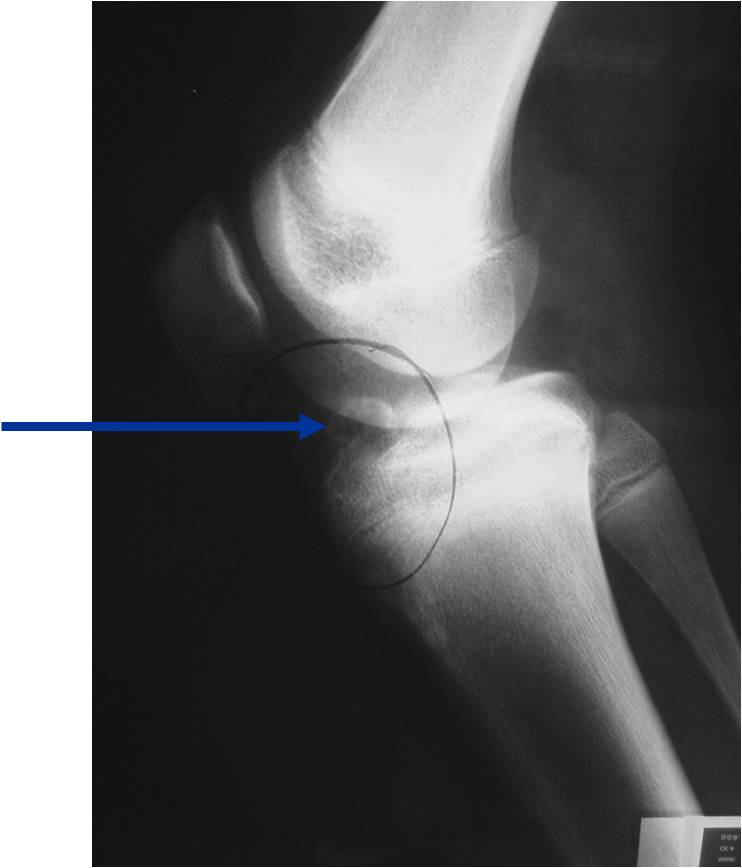

- (CT appearance)

- Most useful for detecting subtle mineralization not apparent on X-rays

- Useful for identifying intact periosteum around any expansile soft tissue component

- surrounding thin reactive shell of bone/mineralization (Egg Shell Rim of Calcification)

- helps place the tumor in a benign category

- helps evaluate:

- bony quality

- extent of bone and cortical destruction

- whether the subchondral plate of bone adjacent to the articular cartilage has been destroyed or is intact